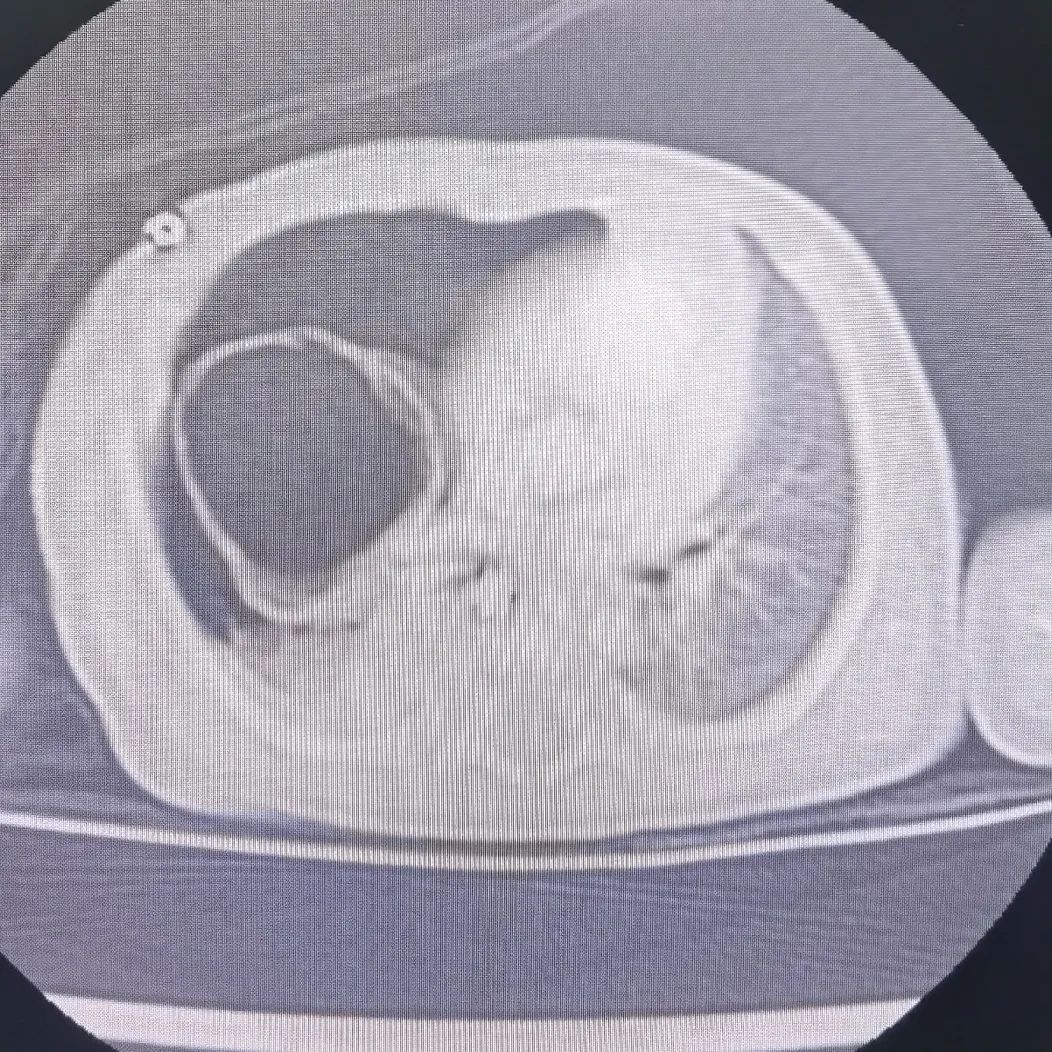

出生仅1700克的小云儿,从降临世界起就没离开过“呼吸战场”:气管插管、肺表面活性物质急救、有创呼吸机支持……命运的考验却接踵而至。生后8天,右侧胸腔突然涌出大量气胸,她再次被插上呼吸机,胸腔闭式引流管里的气泡成了父母心头不断扩大的阴影。CT片上,一个4×5厘米的囊性病灶像颗“炸弹”嵌在右肺,不仅压得右肺完全“罢工”,还把心脏和纵隔挤向左侧,连左肺的呼吸功能也岌岌可危。当地医生看着片子摇头:“这病太凶险,得找北京新生儿外科的专家!”爸爸连夜赶到首都儿童医学中心。王莹盯着片子眉头紧锁:“这是先天性肺气道畸形Ⅰ型,大疱随时可能破裂引发致命气胸,必须尽快手术!”可看着保温箱里插满管子的女儿,爸爸决定再观察几天。

术前胸部CT